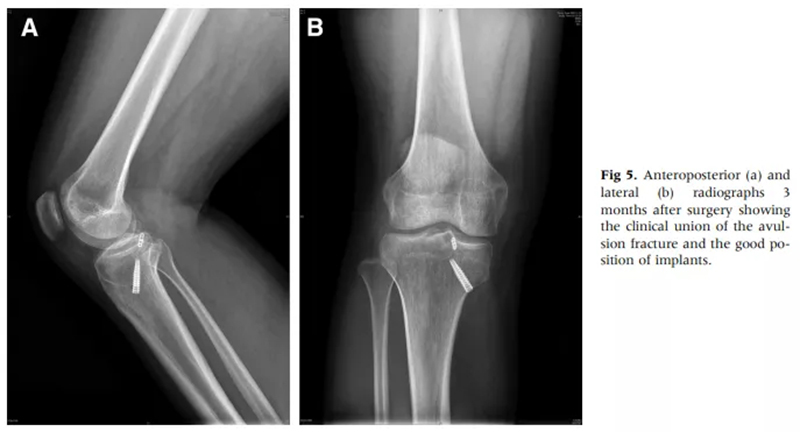

徐醫(yī)附院通過(guò)關(guān)節(jié)鏡微創(chuàng)手術(shù),只需做4個(gè)8mm左右的小切口,通過(guò)做一個(gè)直徑0.45cm、長(zhǎng)約5cm的骨隧道,將長(zhǎng)線(xiàn)環(huán)帶袢鈦板引入關(guān)節(jié)內(nèi),鈦板固定骨折,即可取得很好的穩(wěn)定性,經(jīng)過(guò)長(zhǎng)時(shí)間大規(guī)模的病例累計(jì),形成了40例的總結(jié)分析和評(píng)估,系統(tǒng)地講述了關(guān)節(jié)鏡下微創(chuàng)處理后交叉韌帶撕裂的手術(shù)方式、要點(diǎn)和治療效果,對(duì)行業(yè)發(fā)展也具有很好的借鑒意義。